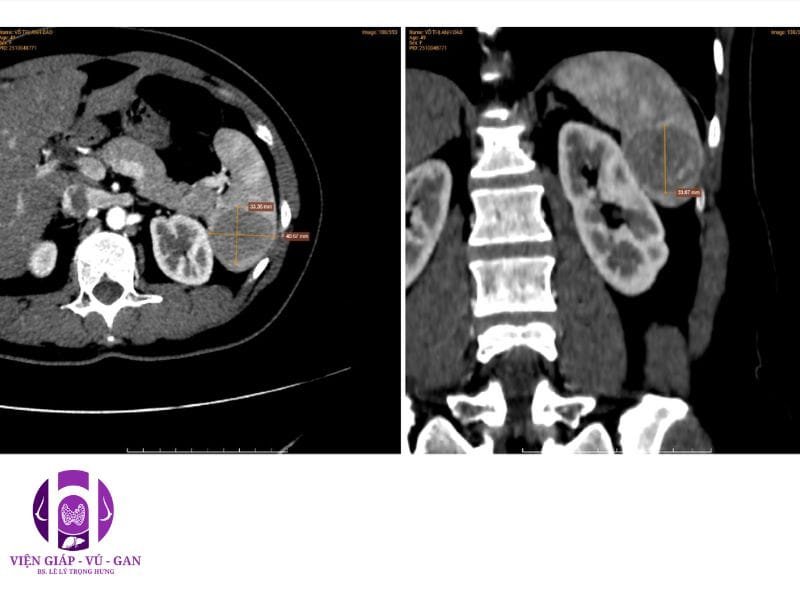

CTSCAN BỤNG CÓ THUỐC:

Lách: không to, tổn thương choán chỗ nhu mô cực dưới, giới hạn rõ, kích thước # 41x33x34mm, giảm nhẹ đậm độ trước tiêm, sau tiêm thuốc cản quang tổn thương bắt thuốc dạng chấm – nốt ở thì động mạch, lấp dần ở thì tĩnh mạch và thì muộn. Vỏ bao lách còn nguyên vẹn, không thâm nhiễm mỡ hay tụ dịch xung quanh.